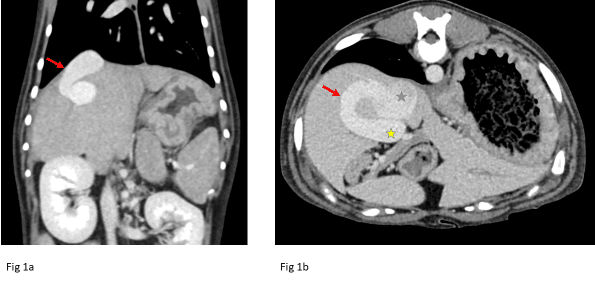

Fig 1a: Example of an intrahepatic portosystemic shunt. Red arrow denotes the shunting vessel. In Fig 1b, the blue star marks the caudal vena cava and the yellow star marks the portal vein.

One of the most common indications for CTA is the evaluation of portosystemic shunts (PSS). Congenital intrahepatic PSS occurs more frequently in large-breed dogs, while congenital extrahepatic PSS is more common in small-breed dogs. It is recommended to further classify either type of shunting prior to surgical intervention (Fig.1). CTA has been shown to be the best modality for characterizing the origin and termination of the shunting vessel as well as evaluating for possible additional shunting vessels that can be missed on ultrasonography or intraoperative mesenteric portovenography.1 Other portal vascular diseases that can be evaluated on CTA include arterioportal fistulas, acquired portosystemic shunting, and evaluation of portal vein thrombosis, which can mimic portal hypertension secondary to liver disease. CTA is the modality of choice for portal vein disease with improved detection compared to ultrasound (Fig. 2).2